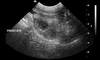

Ultrasonographic findings and most likely dx

myltiple hypoechoic structures within the prostate

Such cavities may represent small cysts or abscesses, but

they are also seen with neoplasia. Such a finding warrants obtaining an

ultrasound-guided transurethral prostatic wash cytology